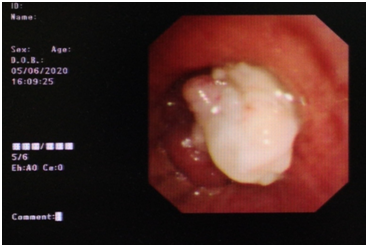

采用特殊波长的光束,利用光化学反应原理治疗恶性肿瘤,这是目前国内外治疗恶性肿瘤的又一种新方法。这种光动力疗法能让肿瘤“见光死”,因此,常被医生称为“圣光”。612日,鄞州人民医院呼吸与危重症科首次利用这种“圣光”成功挽救了一名肺癌晚期患者的生命。

612日,张大伯被送入手术室。手术由俞万钧教授担任主刀,俞万钧首先通过支气管镜,应用高频电刀、冷冻等方法将张大伯气道内部分肿瘤切除,然后通过半导体激光仪发射出630纳米红光,利用光纤传导照射,将气道内肿瘤局部组织及血供破坏,使肿瘤细胞坏死剥落。术后,张大伯气促症状迅速消失。

据鄞州人民医院党委书记俞万钧教授介绍,光动力疗法是一种联合利用光敏剂、光和氧分子,通过光动力学反应选择性地治疗恶性病变的非侵入性肿瘤治疗方法,能通过光敏剂结合在肿瘤部位,在特定波长的激光照射下产生大量的活性氧从而杀伤肿瘤细胞,抑制肿瘤生长。对于肺癌而言,光动力疗法创伤性小、适用性好、靶向性准、可重复治疗,可与其他治疗方法联合。俞万钧表示,作为一种微创疗法,气道腔内早期肺癌患者通过光动力疗法可获得根治,即使不能手术的进展期患者也能有效改善症状、提高生活质量。对于气道肿瘤阻塞的患者,光动力治疗也能取得良好的姑息治疗效果。